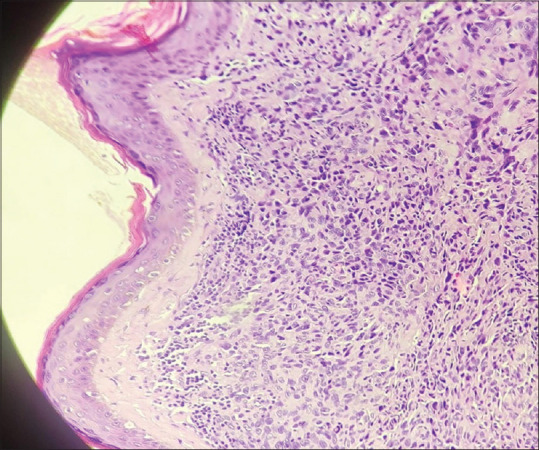

An Elderly Man with Epitheloid Angiosarcoma Presenting as Multiple Scalp Swellings.

老年男性上皮血管肉瘤表现为多发头皮肿胀。